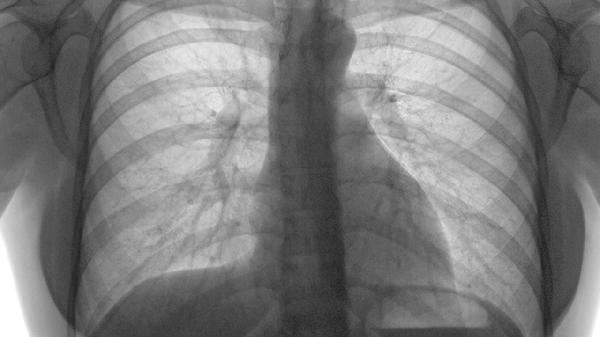

肺癌这个"沉默杀手"每年都在悄悄夺走无数生命。很多人以为只要远离香烟和油烟就安全了,殊不知日常生活中那些看似无害的习惯,可能正在为肺癌埋下隐患。今天要说的这6个隐形推手,比吃错东西更危险!